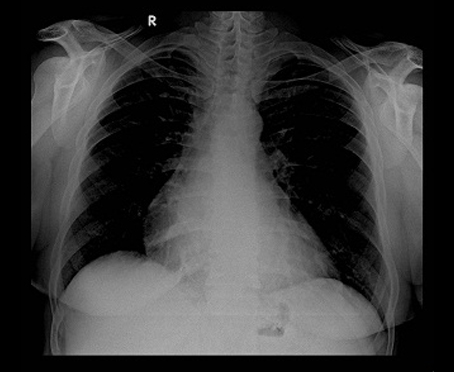

Profect One From Fujifilms The X-ray images with this CR system are always very sharp and clear. The images obtained can be post-processed to suit individual examination. MDRC was the first to install CR system in Haryana.

The Centre has installed two X-ray machines with image intensifier for excellent X-ray investigations in daylight condition at New Railway Road Centre.

50 kW/630 mA high frequency machine MARS 50 from Allengers for high quality X-rays at lower radiation doses.

500 mA Machine of Siemens with motorised table.

MDRC centre at Sector 44, Gurugram has 50 kW/630 mA high frequency machine MARS 50 from Allengers with Image intensifier for high quality x-rays at lower radiation doses. Long cassete for spine and limbs in one film is available. MDRC also has US FDA approved system CR Classic from Carestream for high quality images.

Image Intensifier

Image Intensifier intensifies an image thousands of time its original, thereby enabling the X-ray image to be projected on a monitor and thus be seen in day light. This enables the investigation to be done in day light conditions instead of being done in the dark. There is also better visualization of the organs and hence there is better supervision during investigations and thus better quality of investigations are done. Image intensifier also substantially reduces the radiation dose to the patient and the operator.